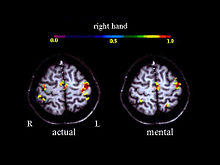

Activation in the motor cortex during motor imagery amounts about 30 % of the level observed during actual performance; Roth et al., 1996.

A large number of functional neuroimaging studies have demonstrated that motor imagery is associated with the specific activation of the neural circuits involved in the early stage of motor control (i.e., motor programming). This circuits includes the supplementary motor area, the primary motor cortex, the inferior parietal cortex, the basal ganglia, and the cerebellum.[20][21] Such physiological data gives strong support about common neural mechanisms of imagery and motor preparation.[22]